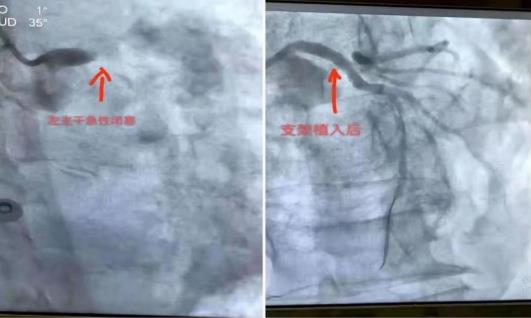

楊老伯,68歲,于2021年6月26日晚上因“反復(fù)胸痛10天,加重伴出冷汗3小時(shí)”來我院“胸痛中心”就診,經(jīng)內(nèi)二科快速診斷為:冠心病,左主干急性閉塞。立即啟動(dòng)綠色通道,送介入室行急診介入手術(shù)。內(nèi)二科黃飛雄主任、賴木喬、蘇偉江三人介入小組以嫻熟的技術(shù)10分鐘快速開通了左主干,術(shù)后由于生命體征不穩(wěn)定,血壓低,直接轉(zhuǎn)ICU進(jìn)行嚴(yán)密監(jiān)護(hù)。經(jīng)ICU、內(nèi)二科會(huì)診適當(dāng)調(diào)整治療方案優(yōu)化治療程序后,患者病情逐漸穩(wěn)定并好轉(zhuǎn),于2021年7月1日可以轉(zhuǎn)到普通病房。